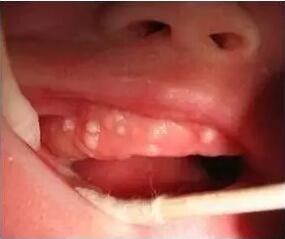

2 吐奶 5个月以下的婴儿,尤其是新生儿,非常容易吐奶、溢奶,主要与两方面因素有关: 一、与新生儿胃容量有关。新生儿胃容量比较小,只有30~60毫升。 二、与新生儿胃部的发育特点有关。 成人胃的入口(贲门)比较紧,而出口(幽门)松。吃完饭后,入口的肌肉会立刻收紧,不管怎么运动,胃里的食物都不会轻易吐出来。再加上出口的肌肉相对较松,食物很快就进入到肠子中了。 而新生儿和成人正相反,入口松、出口紧,吃的奶稍微一晃就返流出来了,所以特别容易溢奶、吐奶。不过这种生理现象会随着月龄的增长、贲门和幽门括约肌的发育而逐渐消失。 在此之前,家长可以通过以下方法来减少溢奶、吐奶: 1、喂奶的时候要注意胃容量,不要因为怕孩子饿而给他喂得太多。 2、喂完奶后,要竖着抱宝宝并为其拍嗝。如果吐奶比较严重,要竖着抱30分钟以上。(点击查看:如何给宝宝拍嗝?) 3、如果是人工喂养的宝宝,家长在喂奶时要将奶瓶倒着竖起,使奶液充满奶嘴,以防止宝宝吃进空气,预防溢奶、吐奶的发生。 4、要在喂奶前给孩子换尿布,否则宝宝很容易因为来回搬动而溢奶、吐奶。 3 “血尿” 很多妈妈在月子里发现,孩子的尿液呈粉红色,但这并不是真正的血尿。因为这种尿液没有红细胞,也没有血红蛋白。出现这种现象主要是由于新生儿的白细胞分解比较多,导致尿酸盐排泄增多,从而出现红色的尿液。 家长看到这种现象不要紧张,注意多喂养、促进排泄,几天之后便会自然消失。 4 新生儿皮疹 很多新生儿都会出现丘疹样红色皮疹,有的会融合成片,有的是皮疹上顶着白尖,类似于脓点,这种现象医学上称为“新生儿中毒性红斑”。 新生儿中毒性红斑的形成原因比较复杂,有的研究认为这是新生儿离开妈妈的子宫和羊水,受到光、空气等外界环境的刺激,出现的非特异性反应,但目前还没有定论。 这种皮疹虽然名字吓人,但如果孩子没有任何不适感,不需要特殊处理,几天之后能自然消退。 5 新生儿脱皮、脱发 新生儿脱皮、脱发是正常的生理现象,与新陈代谢快有关,会随着月龄的增加逐渐消失。 中国大部分地区有“出了月子给孩子剃胎毛”的说法,那么到底要不要给孩子剃胎毛呢?这个家长可以视具体情况而定,不过,剃胎发并不会让宝宝的头发更黑、更浓密,因为这些胎发会随着新陈代谢而脱落,剃头与否并没有什么差别。 6 颤抖、用力、睡不安稳 1 颤抖、抽搐 新生儿颤抖、抽搐,或者突然有声响时出现的惊吓反应,都是正常现象。因为新生儿的神经发育还不够完善,对外界的刺激会发生泛化的反映。 出现这些现象时,只要孩子面色不青紫,稍后就恢复如常,就不是家长们恐惧的“抽风”。抽风通常会伴有面色青紫、意识障碍,抽搐后有嗜睡、昏睡的表现,家长们可以通过这些症状来进行鉴别。 2 挣劲用力 当解开襁褓或脱衣服的时候,新生儿经常会有“挣劲”用力的动作。这是因为新生儿的屈肌张力比较高,上下肢、手足都会自然蜷缩,长时间保持这样的动作会比较累,宝宝会借助“挣劲”用力的动作,来缓解肌肉的疲劳。 3 睡觉不安稳 如果孩子睡觉不安宁,昼夜颠倒,并且经常不明原因的突然大哭,怎么哄都不管用,有可能属于新生儿多动,但这并不属于病态,有可能是新生儿对养育环境不太适应。 宝宝在出生前一直待在子宫内,很依赖妈妈,出生后由阿姨、月嫂来照顾,和妈妈接触得少、闻不到妈妈的味道,就会产生严重不适感。不过也有医生认为,妈妈在孕期里的焦虑、紧张情绪,也会影响到宫内胎儿,宝宝出生后也会受到一定影响。 还有些孩子是抱着就睡,放下就醒,对于这种情况,陈主任认为,家长要学会分辨孩子的各种哭声代表什么需求。如果排除了疾病、饿或者是尿了拉了等原因,家长可以给宝宝一个安静的睡眠环境和合适的睡姿,不要养成抱睡的习惯。 7 新生儿生理性黄疸 如果宝宝在生后2~3天出现黄疸,4~7天达到高峰,7天之后逐渐减轻,但持续时间不超过14天,这种黄疸属于生理性黄疸。它的形成主要与以下三方面因素有关: 1、新生儿红细胞比较多,而且寿命短。我们成人的红细胞寿命是120天,而胎儿、新生儿红细胞的寿命是90~100天。宝宝出生后,大量陈旧红细胞的破坏,会释放出导致黄疸的关键成分“胆红素”。 2、新生儿肝脏处理、代谢胆红素的功能不足。 3、在出生后头几天,宝宝吃得比较少、排泄也不多,不能把肝脏排入肠道的胆红素迅速排泄出去,胆红素在肠道停留的时间长,会被重吸收入体内,也不利于退黄,这个过程医学上称为“肠肝循环”。 在这三方面因素的综合作用下,新生儿便会出现不同程度的黄疸,表现为全身的皮肤发黄,严重的眼睛巩膜也会变黄。 一般生理性黄疸数值不高,可以等待自然消退。母乳喂养的孩子要给孩子按需哺乳,吃配方奶粉的孩子可以适当喝水,来促进胆红素排泄。经常让宝宝晒太阳,也有助于退黄。 但千万不要通过喝葡萄糖糖水的方法来退黄疸,这是不科学的。孩子直接摄入大量的葡萄糖,血糖迅速上升和随后的快速下降,都可能对大脑造成损伤,而且对胆红素排泄没有帮助。 TIPS:如果黄疸出现得过早,在出生后24小时内就出现,或者超过2周黄疸仍然不退,或在出生72小时至2周期间黄疸含量超过12.9㎎,就属于病理性黄疸,一定要及时就医进行蓝光治疗,以免胆红素含量过高,损伤大脑。 8 新生儿白带、月经 有些女宝宝在刚出生的前几天有阴道分泌物或者“月经”,这多是因为妈妈在怀孕期间体内的雌激素、黄体酮通过胎盘进入胎儿体内,使胎儿子宫的腺体分泌增加,所以阴道会分泌白色的黏液,一般4、5天就消失了。 假月经也是同样的道理,胎儿受到妈妈影响,体内雌激素水平比较高,出生后雌激素水平迅速下降,子宫内膜开始脱落并流血,即假月经。 正常情况下,假月经的量通常很少,无需特殊处理,家长只要做好宝宝私处的护理就好。但如果出血量特别多,要警惕是否是新生儿出血症,应该及时带宝宝到医院就诊。 9 新生儿乳房肿大或乳头凹陷 在中国很多地区都有给孩子挤乳头的说法,其实无论是男宝宝或女宝宝,都可能出现乳头肿大或凹陷的现象,和前面提到的白带、假月经一样,也是受母体激素的影响而产生的,不需要进行干预。 经统计,约有50%的新生儿会发生乳头凹陷,到成年后,真正的乳头凹陷患者不足7%,所以家长没必要给新生儿挤乳头。 10 生理性体重下降 出生后的1周里,很多宝宝的体重不仅不增长,反而会降低,也就是俗称的“掉水膘”。 这是因为新生儿的排泄量比胎儿期更多,大便、小便、皮肤蒸发和肺部的呼吸运动都会消耗水分。但只要体重下降不超过出生体重的10%,就是正常的;如果体重下降超过10%,则说明喂养存在问题。 11 频繁打嗝 新生儿口腔内,包括牙龈、牙床或者硬颌部位,出现的白色点状小隆起,医学上称为“上皮珠”,也就是老百姓所说的马牙。 过去有“擦马牙”的习俗,老人会用毛巾裹着手指用力将马牙擦掉,实际这是很危险的,特别容易造成口腔内的感染。近年来随着医学常识的普及,很多家长已经认识到这种情况其实是正常的,过3~5个月就会自然消失,因此没有必要擦马牙。 陈玉琴主任表示: 以上这些情况都是新生儿特有的生理现象,是暂时的,随着年龄增长会逐渐消失,不是病态,所以,家长没必要过分担心。